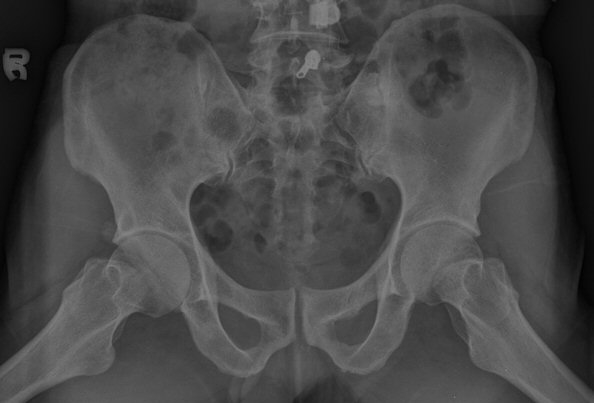

¾ûµ¢ÀÌ °üÀý Á¾´Ü¸é°Ë»ç¿¡¼­ ƯÀÌ ¼Ò°ßÀ» º¸ÀÌÁö ¾ÊÀ½(»çÁø 1).

ÃÊÁø ½Ã ½ÃÇàÇÑ ¹æ»ç¼± ÃÔ¿µ»ó ÀüÇÏÀ屨 ºÎÀ§¿¡¼­ ¼®È¸È­ À½¿µÀÌ °üÂûµÇ°í, 3ÁÖ ÈÄ ½ÃÇàÇÑ ÃÔ¿µ¿¡¼­

¼®È¸È­ À½¿µ ¼Ò½ÇÀÌ È®ÀεÊ.